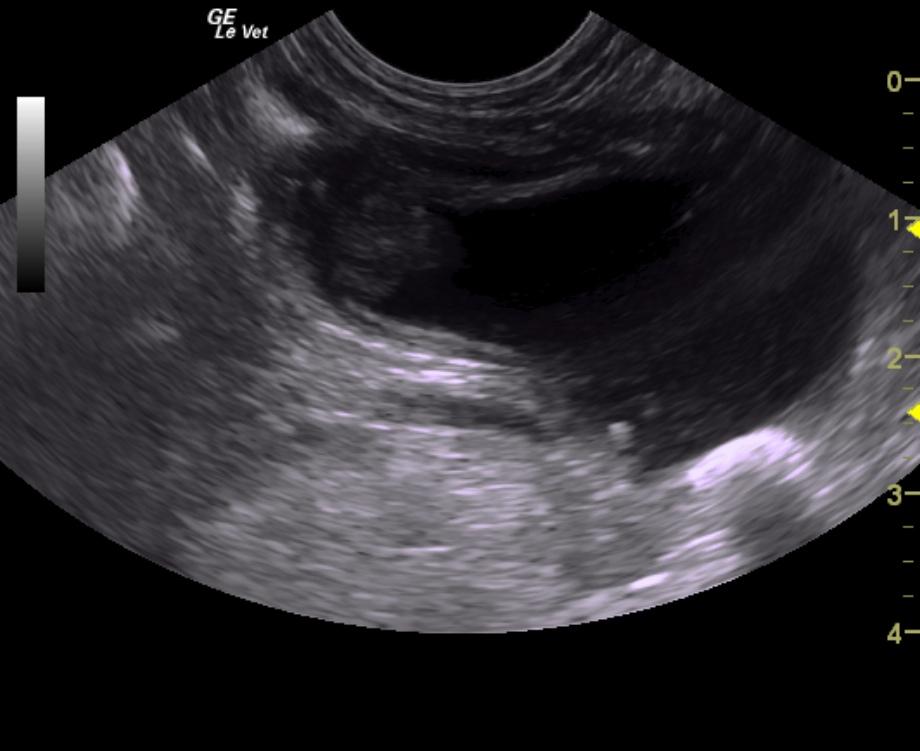

A 14-year-old neutered male Poodle dog was presented for evaluation of chronic hematuria with a history of calcium oxalate calculi and evidence of urinary tract infection.